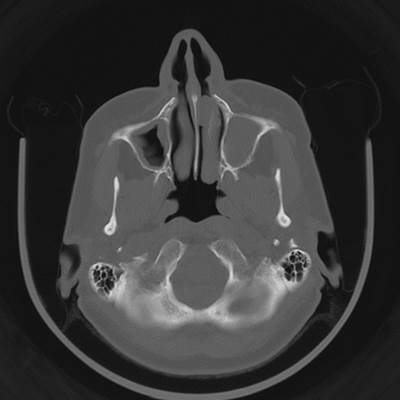

Полипозный этмоидит

Полипозный этмоидит 110 фото